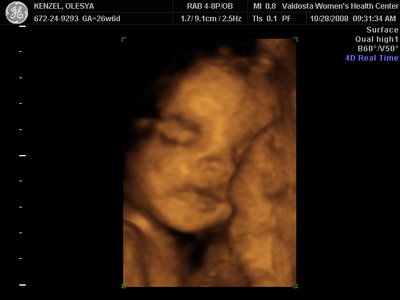

Ксюнь, а мы вообще не поняли. Она на всех фотках разная, да еще размытость такая. Пуповина то на носу болталась, то руками-ногами закрывалась. Главное что четкости нет совсем. Лоб у мужа тоже большой, а носы и губы зачастую на 3Д-4Д выходят разамазанно-пухло-приплюснутыми Поставлю для наглядности фотку моей средней-Джианки с 3Д УЗИ, там видно черты намного лучше и она на себя ту похожа сейчас, хотя родилась мне совсем на фото УЗИ не казалась похожей.

| Вложения: |

KENZEL,OLESYA_3.JPG [ 56.84 КБ | Просмотров: 1428 ]

Еще одна Джианнка:

KENZEL,OLESYA_5.JPG [ 60.02 КБ | Просмотров: 1513 ]